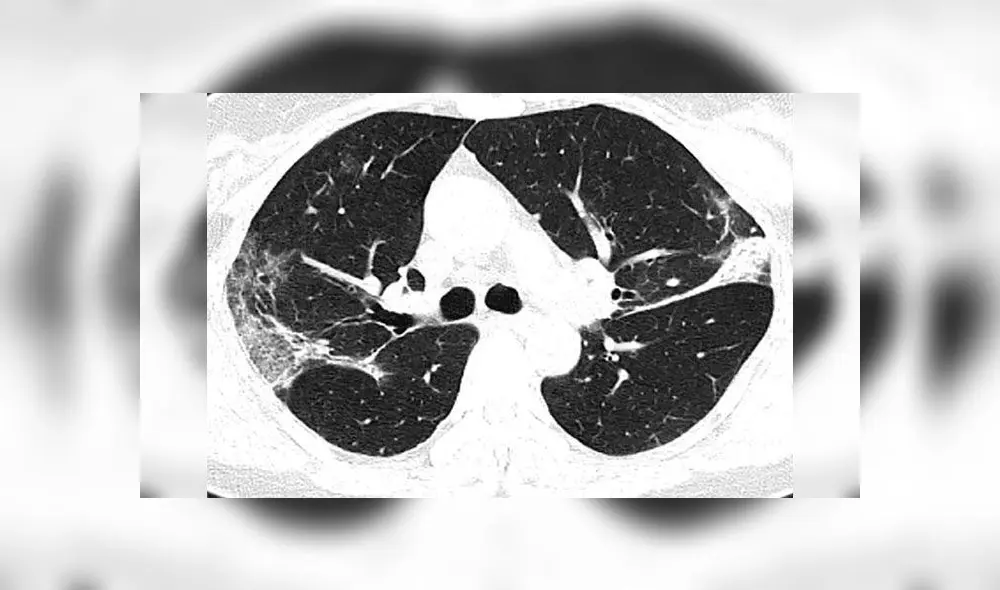

También se ven manchas blancas en los pulmones de una mujer de 45 años que dio positivo por el virus tras regresar de Japón.

Estas anomalías indican un llenado parcial de espacios de aire en los pulmones, de forma parecida a lo registrado en pacientes con enfermedades como el SARS y el MERS.